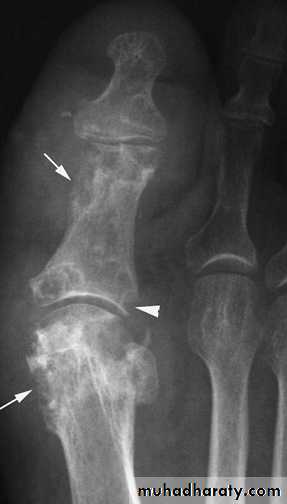

Radiographs

Radiograph of the joint: Although frequently normal, a radiograph may disclose important information.It may help in diagnosing an unsuspected fracture, osteonecrosis, osteoarthritis, or a juxtaarticular bone tumor.

The presence of chondrocalcinosis, a radiologic feature of CPPD disease, increases suspicion for a pseudogout attack.

Tumor, chronic fungal or mycobacterial infection, and other indolent destructive processes may be revealed.